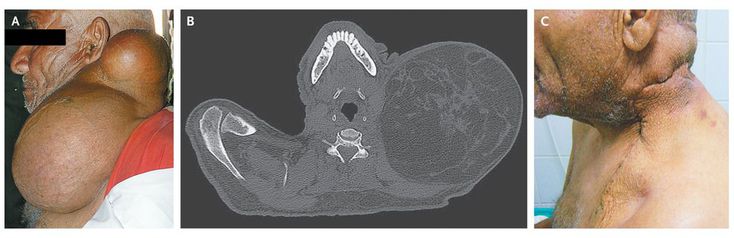

A 68-year-old man with no notable medical history presented with left cervical swelling that had been slowly increasing in size for 3 years. The patient was afebrile. The physical examination was unremarkable except for large swelling of the left side of the neck (Panel A), which caused limited mobility of the neck. The neck mass was firm, mobile, and nontender. There was no surrounding lymphadenopathy, and there were no signs of compression. Computed tomography revealed that the mass was heterogeneous and measured 27 cm by 16 cm by 17 cm (Panel B). A diagnosis of liposarcoma was considered, given the patient's age and the size of the mass. Histologic examination of a specimen obtained by surgical biopsy revealed features consistent with a hibernoma. Hibernomas are uncommon, benign soft-tissue tumors that histologically mimic brown fat. The most common anatomical locations of hibernomas are the neck, axillae, mediastinum, and periaortic and perirenal zones. The patient underwent total resection of the mass (Panel C); further histologic studies showed lobules of various sizes with many adipocytes and fat vacuoles and no atypical cells. At the 6-month follow-up, there had been no recurrence.